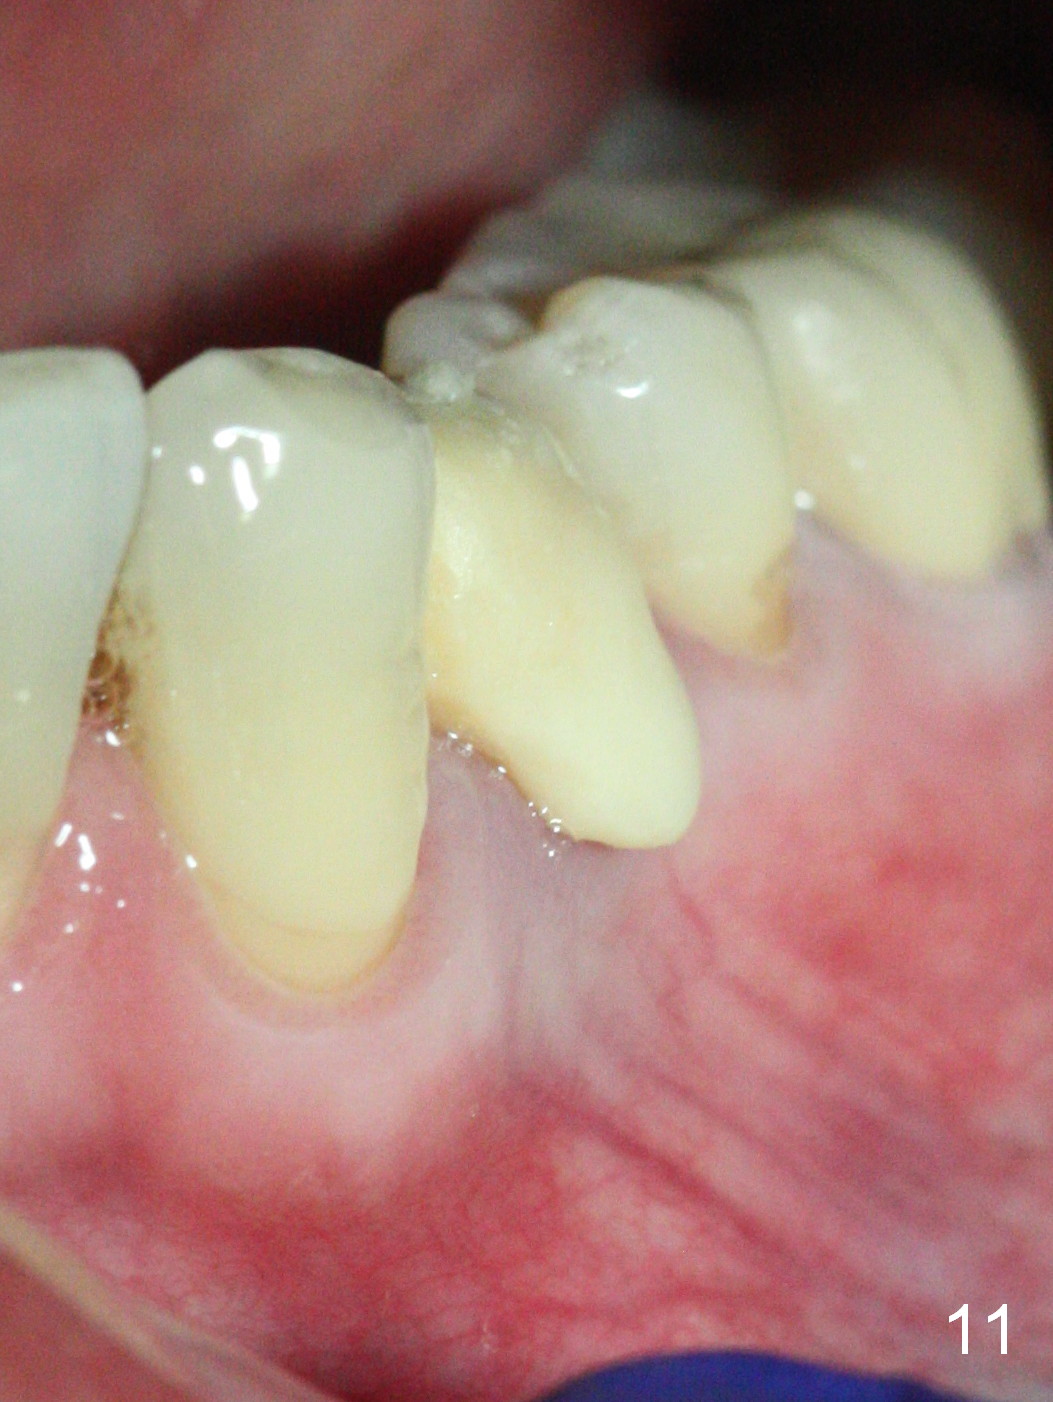

The implant seems to have osteointegrated 4 months postop (Fig.9). When a permanent crown is fabricated, it should have normal occlusal and buccal contour (from Fig.11 (provisional) to 12 red and black curved lines) as well as the buccal cervical extension (Fig.12 to cover the buccal gingiva (Fig.10 *). If the lingual margin of the abutment is too prominent, return the case and the abutment will be changed to the one with 2 mm cuff (existing 3 mm). The lingual margin of the abutment will be trimmed. The patient is not pleased with the short buccal margin of the crown after cementation (Fig.13). In fact the provisional should have been fabricated so that the its buccal margin should be subgingival and within the gingival outline. It may prevent buccal plate collapse. In fact the crown dislodges 1 year post cementation. The lingual margin is prep lower to increase the abutment height. Impression is taken. Although the access hole is unnecessary for cementation, it acts as an escape hole so that there is no excess cement cervically (Fig.14-18).